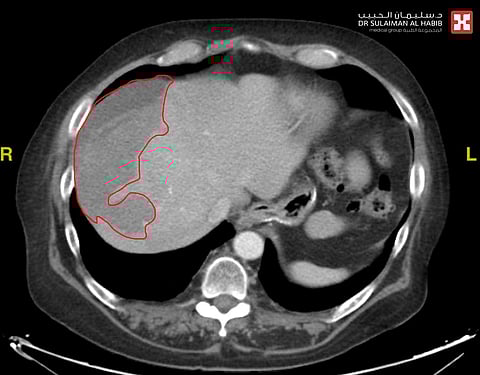

كما أفاد بأنّ نتائج الفحوصات أكّدت وجود نزيف حادّ بالجزء العلوي من الكبد، ناتج عن التوسع بالأوعية الدموية، أو ما يُعرف طبيًّا باسم "تمدد الأوعية الدموية الكاذب - Pseudoaneurysm"، وعقب الانتهاء من دراسة كافة النتائج، تمّ تحويل المراجع لوحدة القسطرة والأشعة التداخلية؛ لإجراء التدخل الطبي بالقسطرة، والذي استغرق "50" دقيقة فقط، تحت التخدير الموضعي، وتم فيه عمل فتحة صغيرة لا تتجاوز "2" ملم في شريان الفخذ، عن طريق استخدام جهاز ملاحة الأشعة التداخلية؛ إذ تم الوصول إلى شريان الكبد النازف، والسيطرة عليه وإيقاف النزيف، عن طريق أدوات طبية متقدمة مكونة من لفائف طبية خاصة مصنوعة من مادة "التيتانيوم"، والمخصصة لمثل هذه الحالات الطارئة.